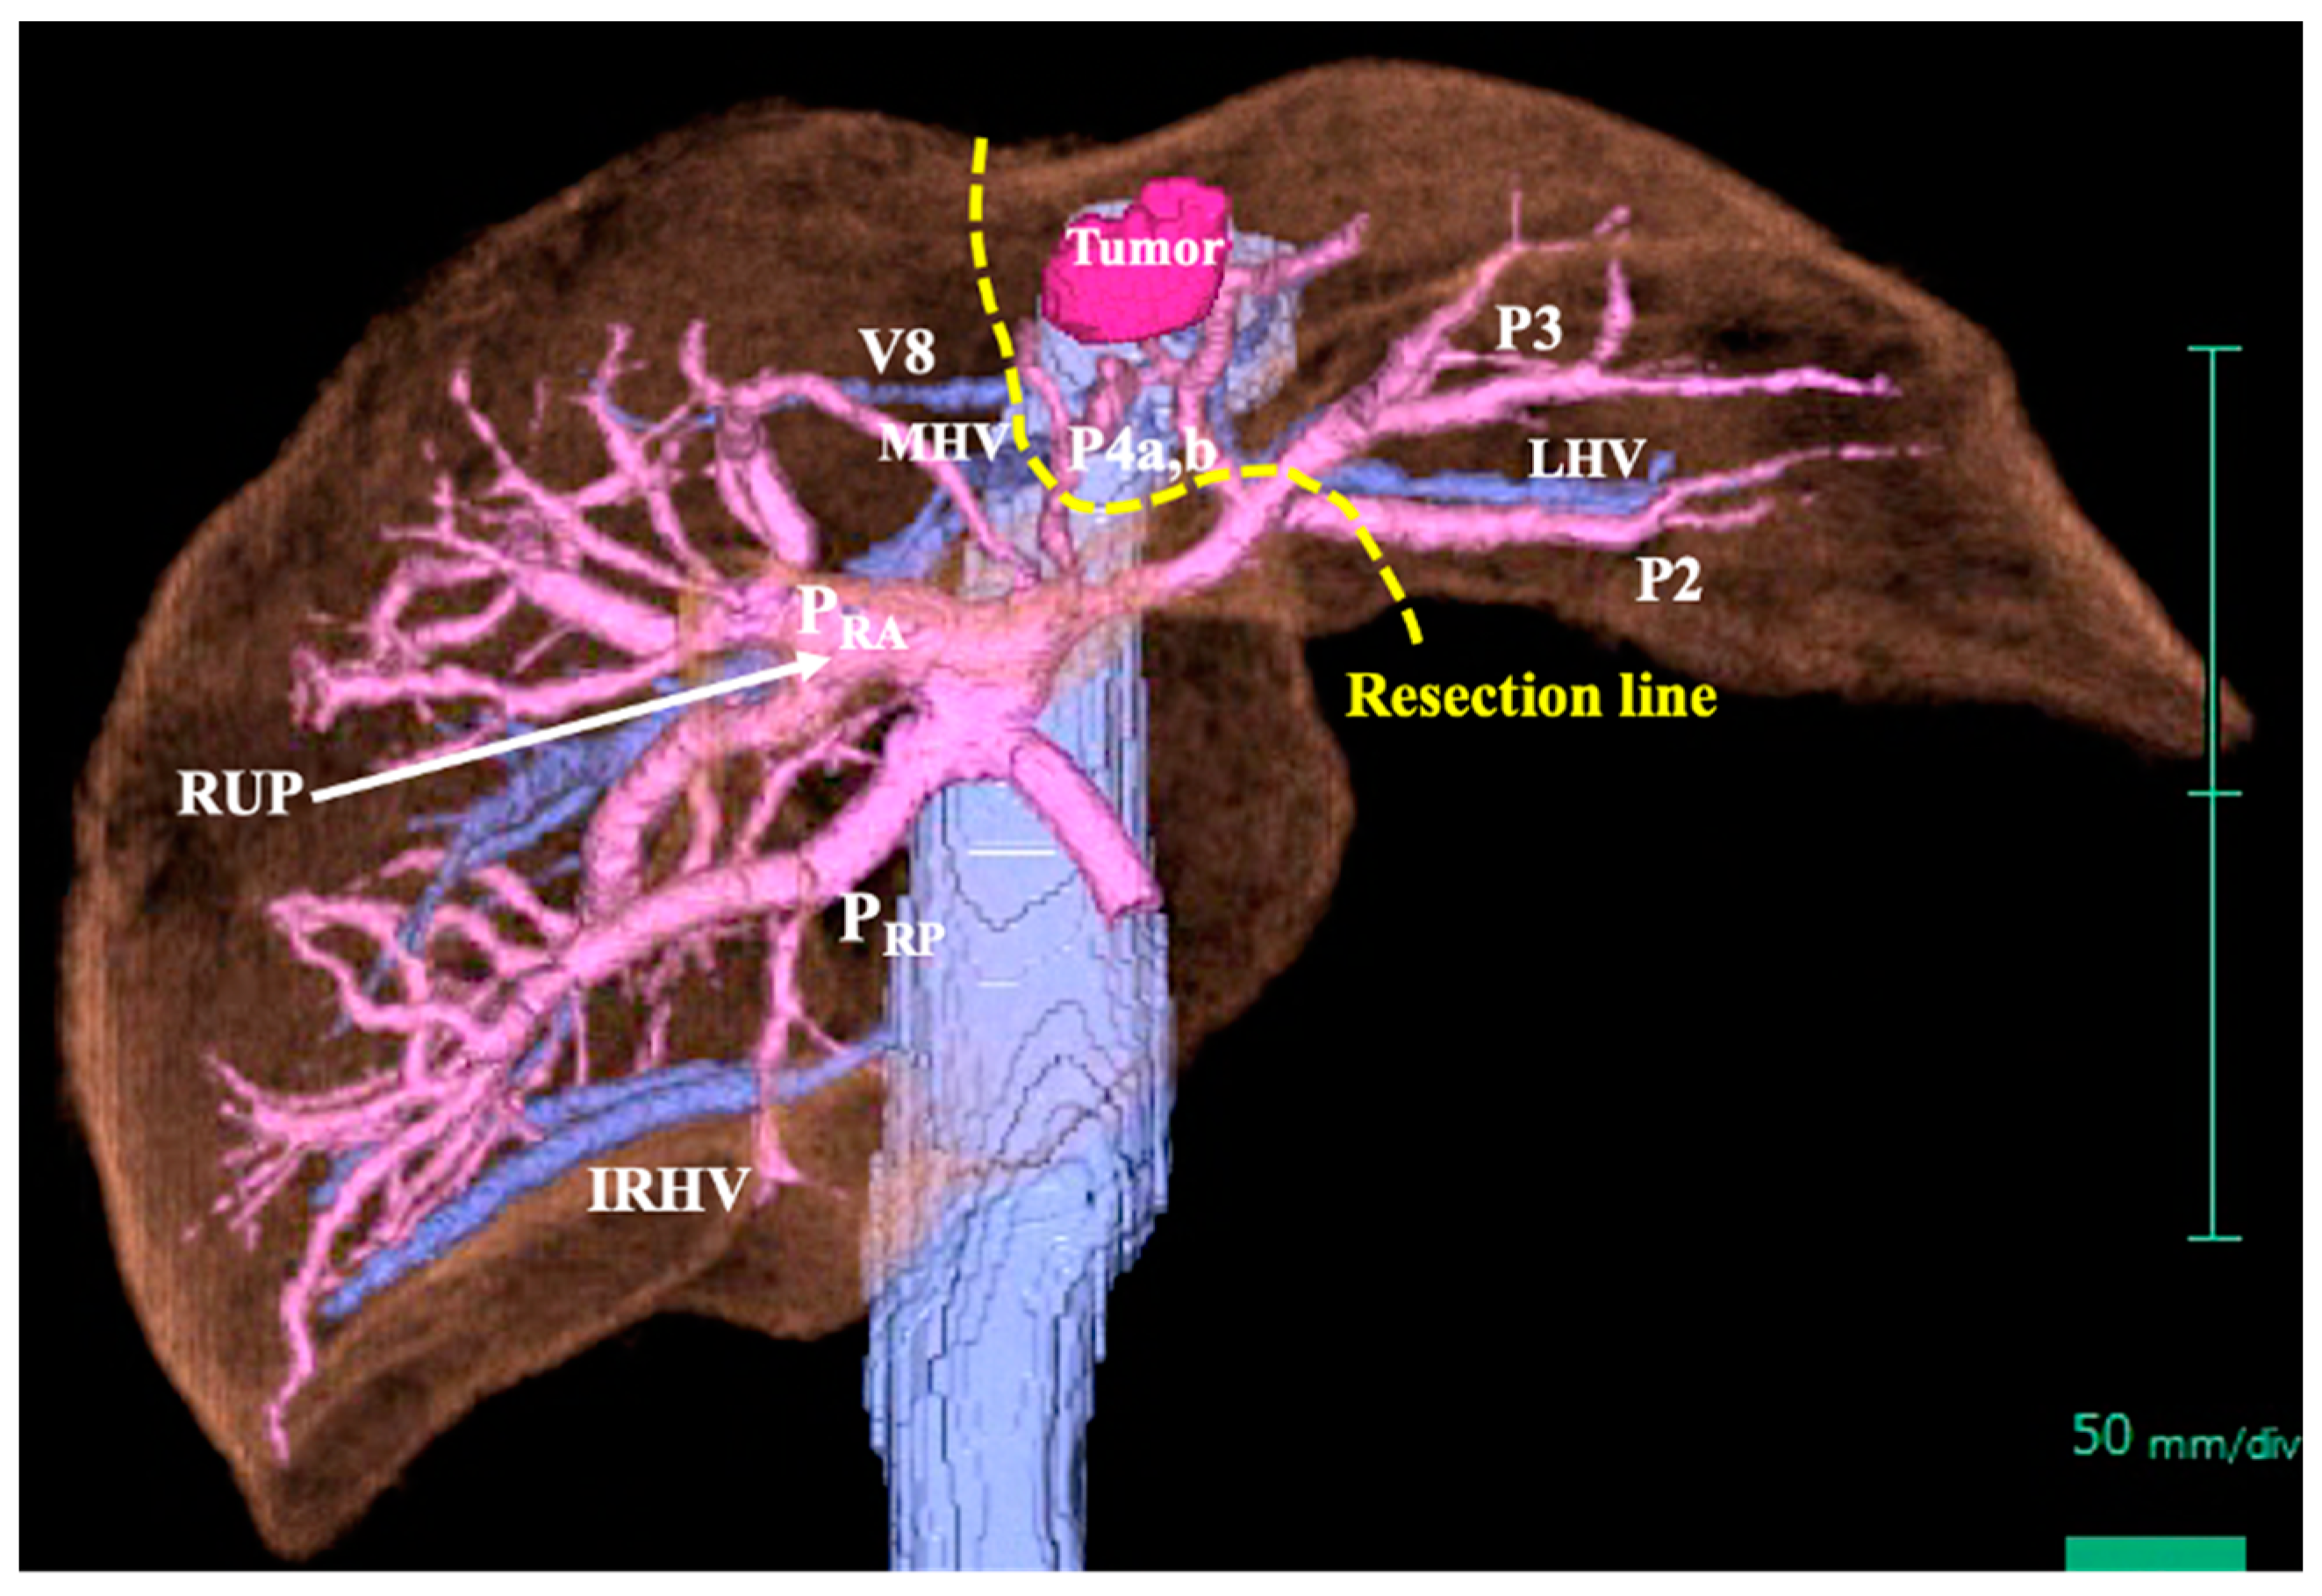

2. Case Report